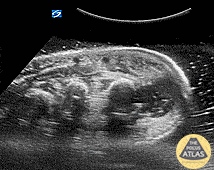

Periosteal Hand Abscess Pt is an IVDA with a recent lanced boil, total hand swelling and pain with movement. Water bath demonstrates a large collection periosteally which underwent washout and drainage in the OR for concern of early osteomyelitis. Dr. Dustin Morrow